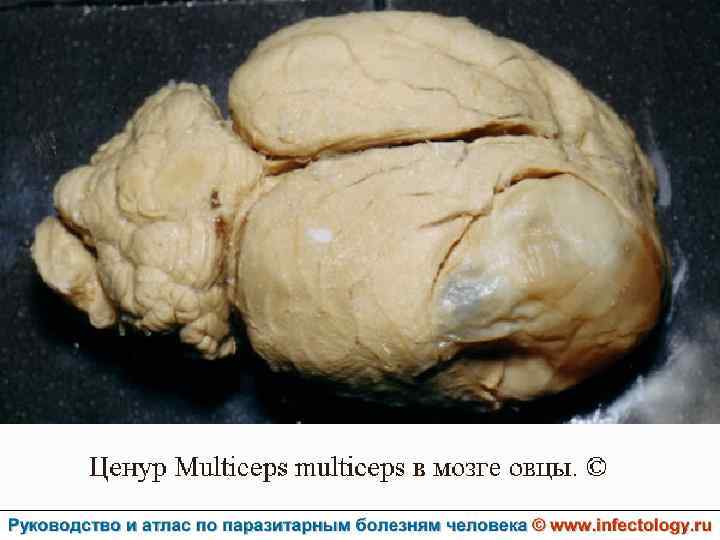

Ценуроз (шифр по МКБ 10 – B 71. 8)– спорадически встречающееся заболевание человека, вызываемое личиночной формой (ценуром) гельминтов рода Multiceps, половозрелые формы которых паразитируют у собак и диких волчьих. . Проявляется разнообразными клиническими симптомами в зависимости от вида паразита.